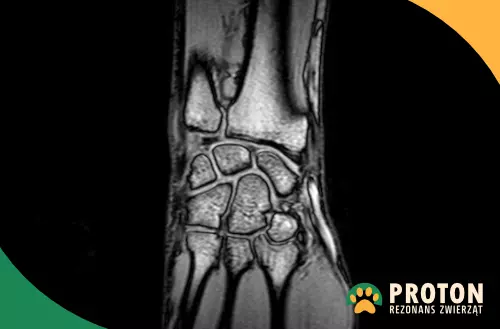

Co jest widoczne w rezonansie nadgarstka – przedniej łapy?

• 7 kości nadgarstka ułożonych w dwa rzędy,

• staw przedramienno-nadgarstkowy, staw śródnadgarstkowy i staw nadgarstkowo-śródręczny wraz z otaczającymi więzadłami,

• chrząstka włóknista dłoniowa nadgarstka,

• krążek promieniowo-łokciowy,

• ścięgna mięśni odpowiedzialne za ruchy nadgarstka.

Rezonans weterynaryjny nadgarstka - zdjęcia

Obraz RM łapy

Rezonans łapy